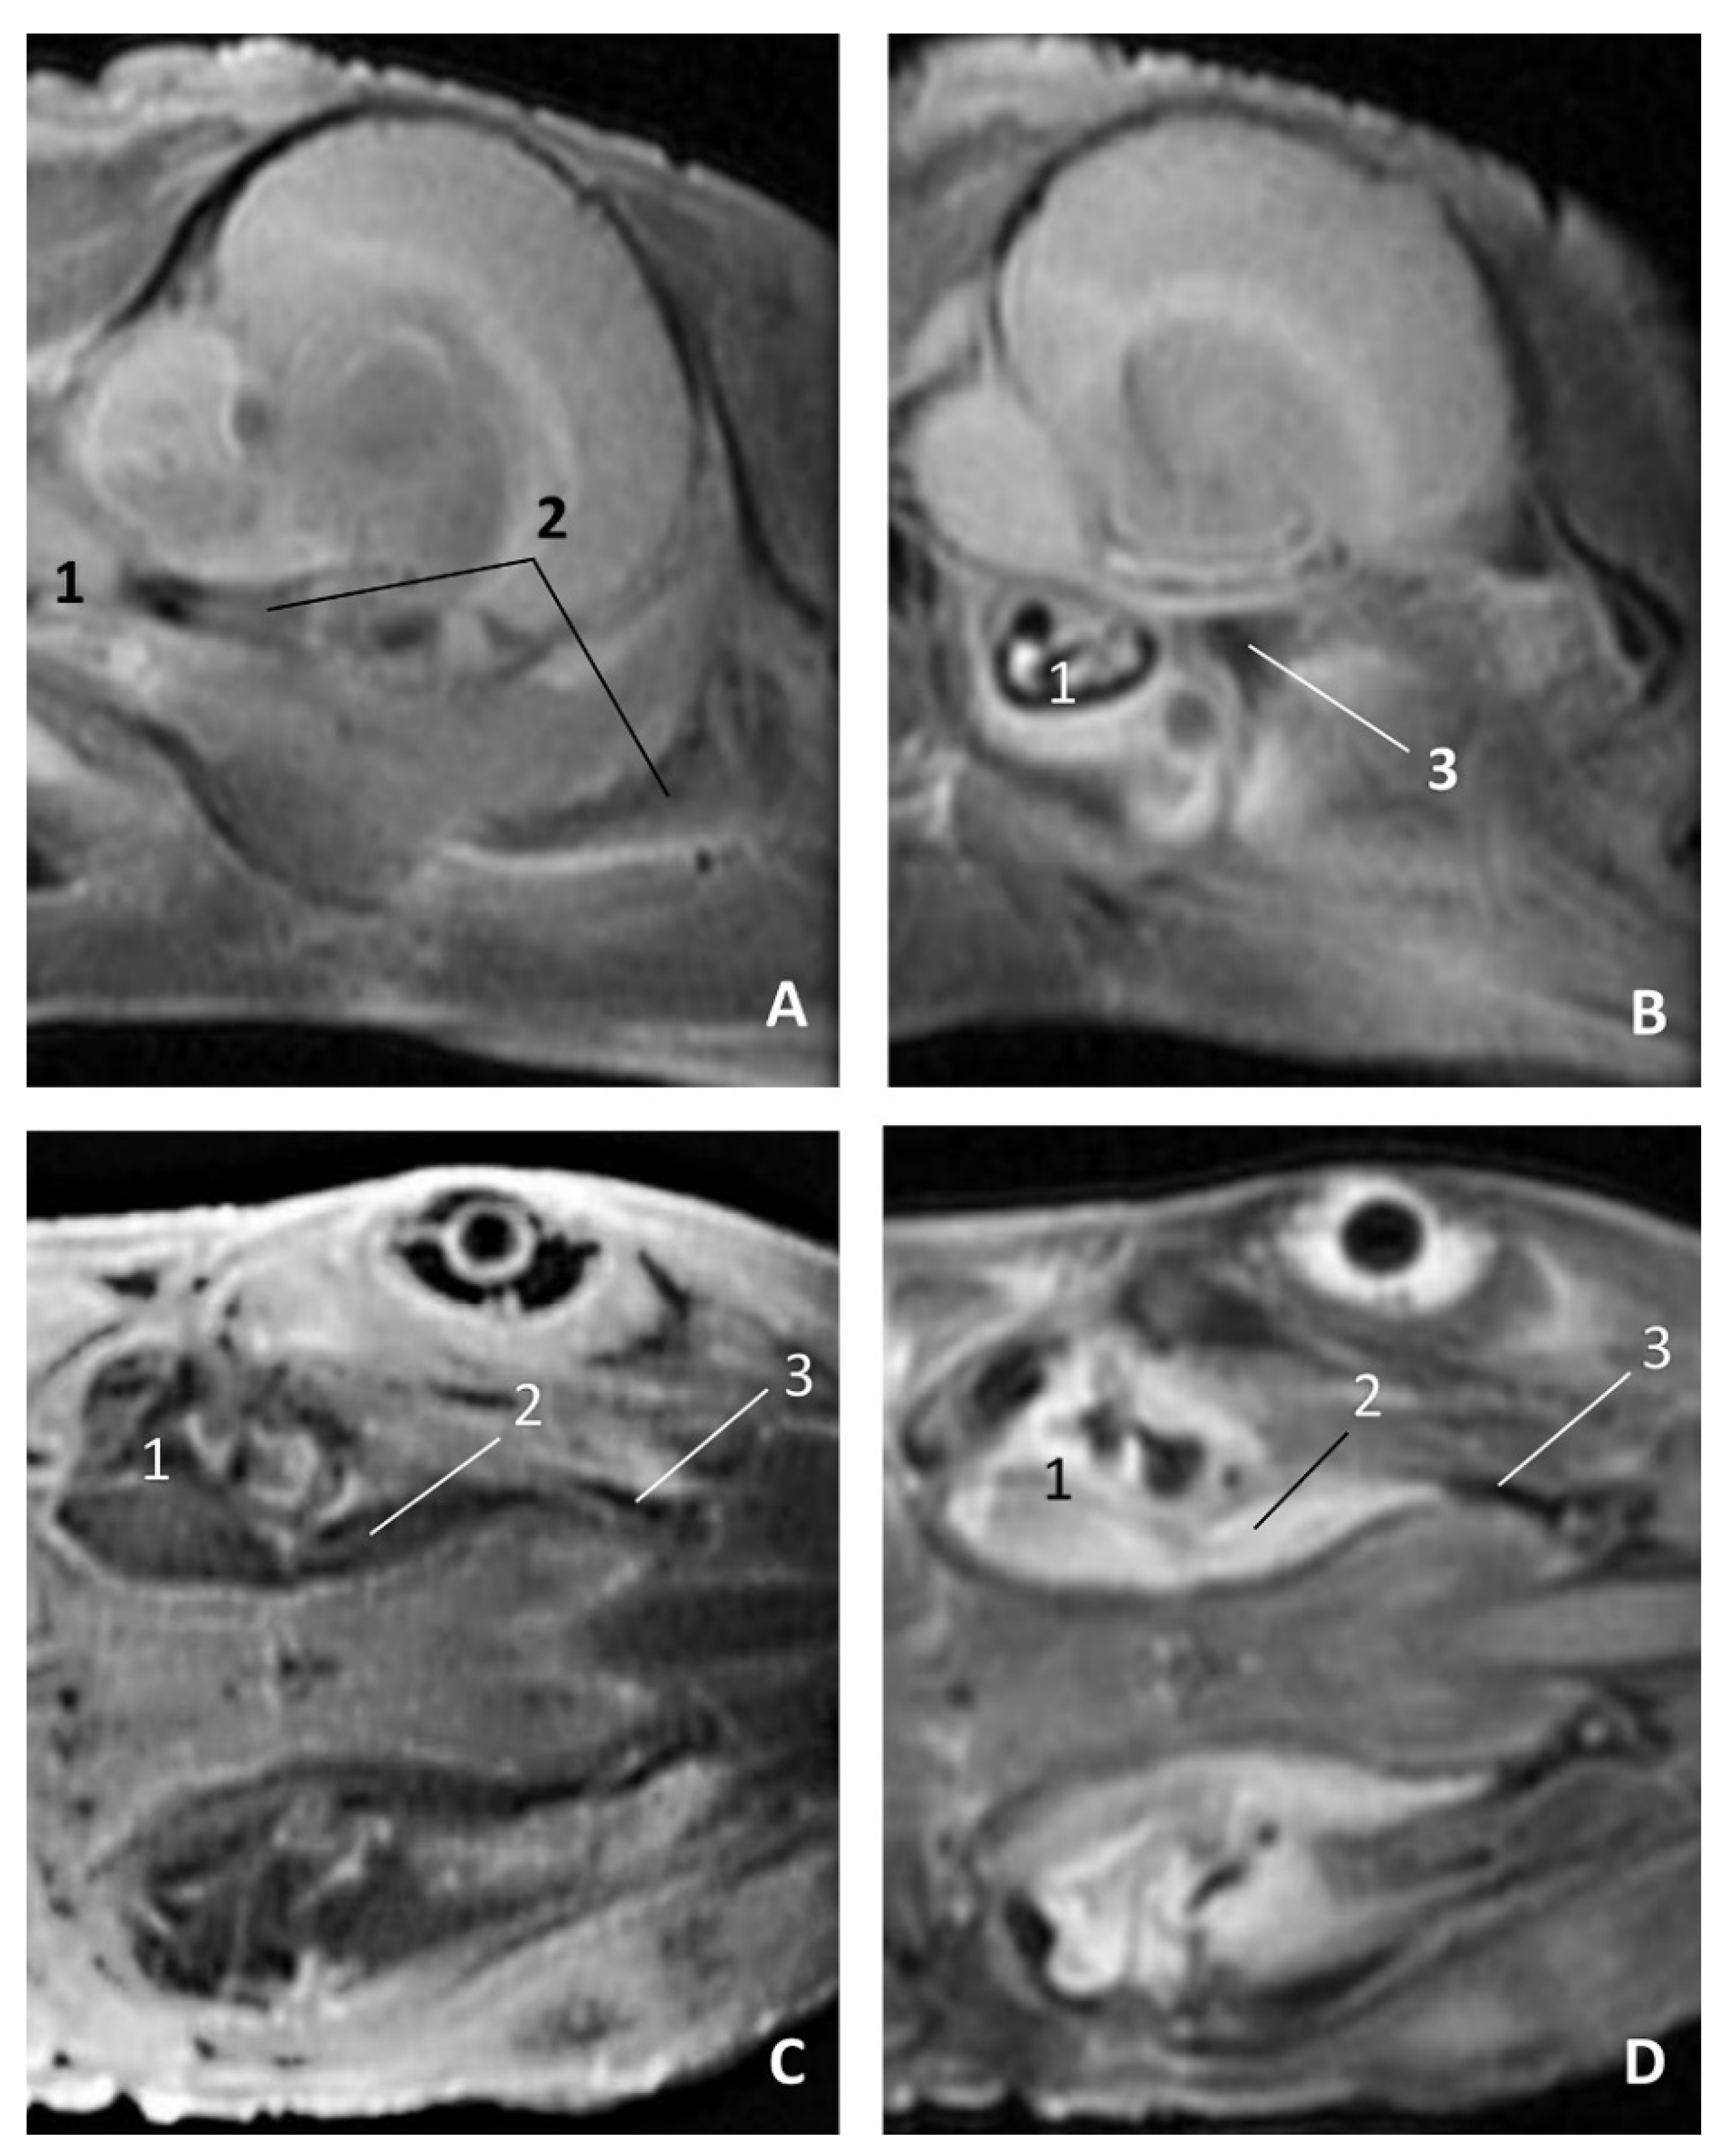

In MRI, we can appreciate, in early fetal stages, a bilateral structure within the laryngopharyngeal cavity, each named as a pharyngeal diverticulum of the auditory tube (PDAT). These are connected through the musculotubaric channel with the middle ear (temporal bone: petrous and tympanic part). In a young Delphinus delphis fetus (dde3), it appears in sagittal sections as a hyper/hypointense area seen caudal and rostrally, respectively (Figure 26A,B), and also in coronal sections (Figure 26C,D).

Figure 26.

Images of the pharyngeal cavity. MR sagittal and coronal images are oriented so that the rostral is to the right. (A) T1 SE sagittal, (B) T2 FrFSE sagittal, (C) T1 SE coronal and (D) T2 FrFSE coronal planes. 4 months, dde3. 1, Inner and middle ear; 2, Pharyngeal diverticulum of the auditory tube.

In older Delphinus delphis fetuses (dde5, dde8, dde11) this double space at both sides of the laryngopharynx is more evident and shows the same intensity, but now we can distinguish the vascular area (hyperintense) and the air-filled area (hypointense) (Figure 27, Figure 28, Figure 29, Figure 30 and Figure 31).